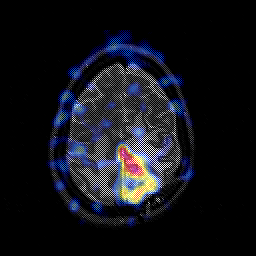

Glioblastoma multiforme overlay -- Slice #41

[Home][Help][Clinical][Tour 1][Tour 2][Tour 3] Slice 41